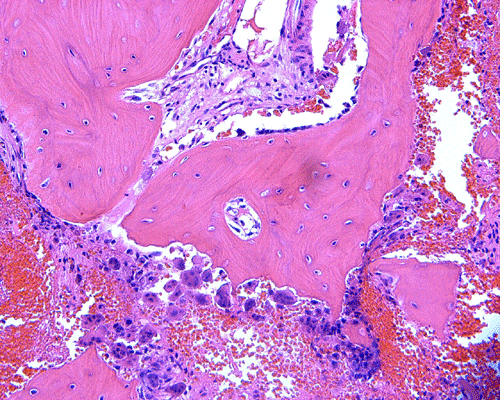

Pathology of the case: The specimen consists of multiple small pieces of irregular tissue fragments obtained by curretage. Histologically, the lesion tumor consists of bland spindled cells embedded in a collagenous matrix and arranged in a storiform pattern with frequent hemorrhage (Panel B). Entrapped residual bone associated with foci of osteoclastic type giant cells are present (Panel C). A scant number of epithelial islands are also scattered within this spindle cell background (Panel D, E, and F). On high magnification, no significant nuclear atypia or pleomorphism is noted in either the spindle cell or epithelial cell components. In other parts of the specimen, the spindle cell tumor is admixed with spiculated fragments of woven bone rimmed by osteoblasts (Panel H, I, and J). Small islandsIt of epithelial cells are also noted in these areas (Arrow in Panel H).

On immunohistochemistry, the epithelial islands are positive for cytokeratin AE1 and AE3 (Panel K and L). Both the spindle cell component and epithelial cells are positive for vimentin (Panel M).

Differentiated (osteofibrous dysplasia-like) adamantinomas are exclusively intracortical. The microscopic appearance of differentiated adamantinoma resembles osteofibrous dysplasia. Spindled cells with a storiform pattern mingle with fragments of bone. The bony fragments are typically rimmed by osteoblasts and exhibit gradual progression from woven to lamellar bone as one moves from the center to the periphery of the lesion. Epithelial islands can be seen interspersed focally within the aforementioned osteofibrous dysplasia-like stroma. The epithelial component is much less prominent than in the classic variety of adamantinoma. Immunohistochemistry for cytokeratin is a very useful adjunct to demonstrate these scattered epithelial elements and they can be very small and subtle as demonstrated in this case.